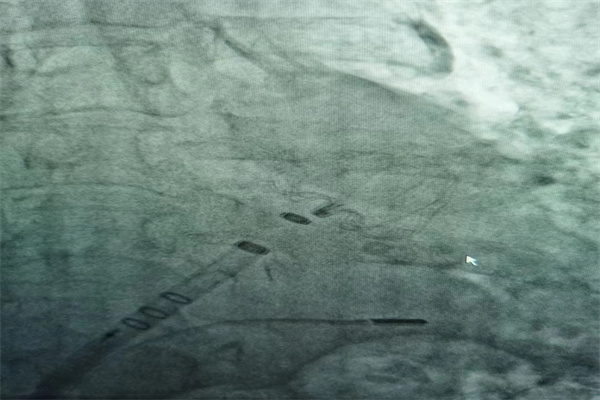

歷時(shí)2個(gè)半小時(shí),最終為劉奶奶順利植入WATCHMAN 27mm封堵器,術(shù)后再經(jīng)ICES觀察封堵效果良好,壓縮比18 %,符合PASS原則。整個(gè)手術(shù)過程,劉奶奶完全清醒、無不適感。